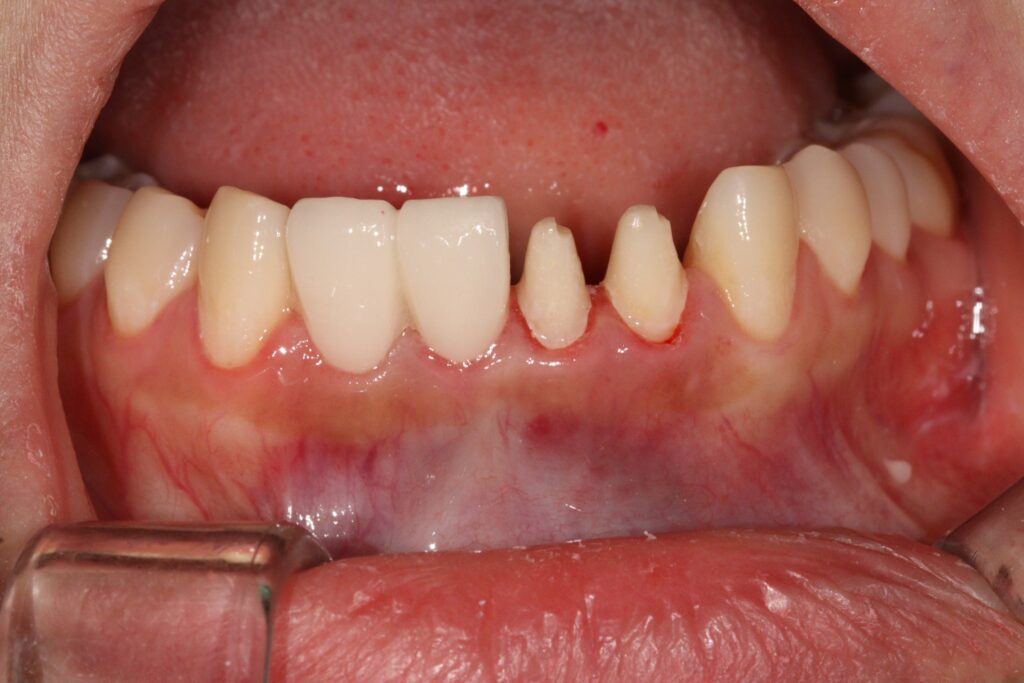

오늘은 아래 앞니 보철 치료 후

극심한 통증으로 인해 보철물을 제거하고

신경치료 후 재크라운으로 자연치아살리기를

진행하신 환자분을 소개해 드리려고 합니다.

환자분께서는 아래 앞니 보철 후 갑자기

극심한 통증으로 인해 내원해 주셨습니다.

급성 치수염으로 인해 기존 보철물을 제거하고

신경치료가 필요한 상황이었는데요.

기존 보철물의 경우 두개씩 치아를 연결해

치아 사이사이 관리가 잘 되지 않아

잇몸 반응도 좋지 않아 붉은 염증이 계속되고

있는 점도 확인하였는데요.

모든 크라운을 제거해보니 이전 치과에서

너무 치아삭제를 많이 해서 치수염이 발생했던 것으로

판단되었습니다.